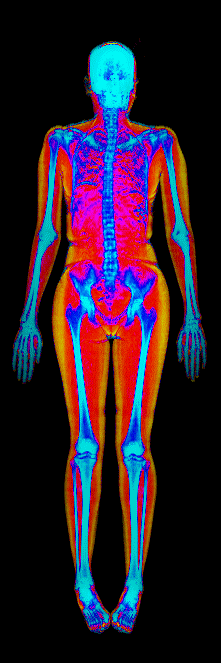

Each colorized scan shows the distribution of fat tissue (shown in warmer colors) and lean tissue (cooler colors) throughout the body. Compare your own DEXA scan to others in your range, or see what different body fat levels actually look like on a scan.

Female DEXA Scans by Body Fat %

15 to 20% body fat

20 to 25% body fat

25 to 30% body fat